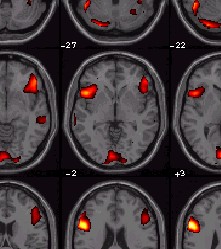

Visualisierung (SPM2)

• Render       Sections     Slices

Sections

• geht nur im Resultate-Menü:

• Resultate, Kontrast auswählen, Schwelle setzen